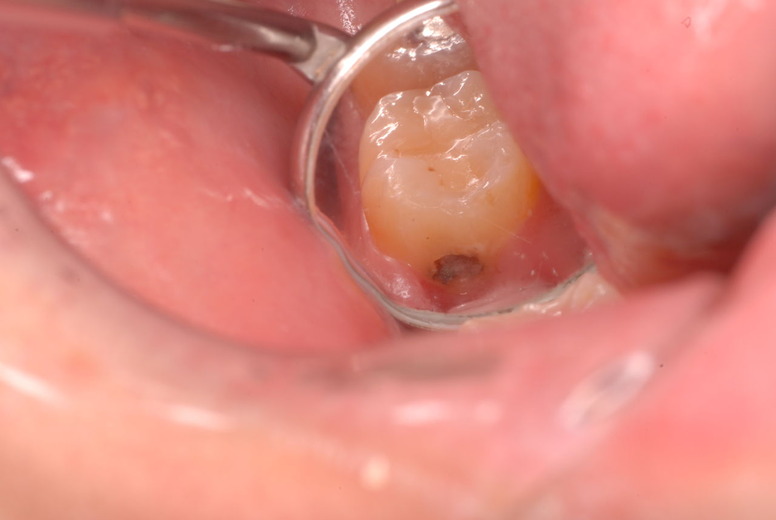

写真左下の親知らずが痛くなり抜歯しました。その後歯茎を除去して虫歯を露出させる処置を二回ほどしています。

レントゲンでは小さいですが、こう言う虫歯が一番怖いのです。

治療の成功率は極めて悪くすぐ再発しやすいのです。